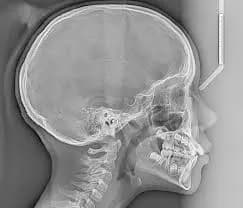

An OPG (Orthopantomogram) is a single panoramic X-ray showing the teeth, jaws, and surrounding structures—commonly used in dental and emergency settings for quick, broad diagnosis. A Lateral Cephalogram (Lat Ceph) is a side-view X-ray of the face used to measure jaw alignment and bite, especially for orthodontic planning.

Images are calibrated for accurate tracing of dental and skeletal landmarks

Supports overjet, overbite, skeletal class, and airway analysis

Designed for minimal radiation exposure in young patients